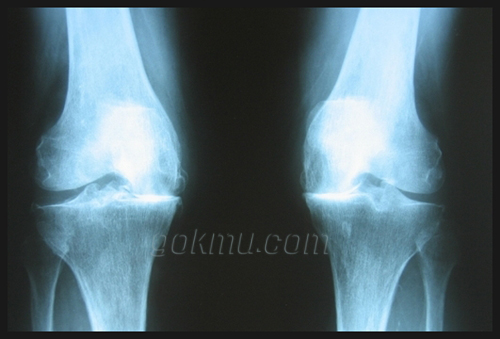

여러 가지 원인으로 무릎 관절의 통증이 있는 경우 다양한 진단법이 제시되고 있다. 환자의 병력과 면밀한 이학적 검사로 대개의 질환을 추정할 수 있고, 단순 방사선 사진과 스트레스 부하 방사선 사진 및 자기 공명 영상 등의 비침습적인 방법으로 관절 내부의 상태를 정확히 진단 가능하며 경우에 따라서는 진단적 목적으로 관절경을 시행하여 관절 내부 병변을 확진할 수 있다. 특히 의공학의 발전으로 인해 자기 공명 영상이 진단에 있어서 필수적인 요소로 확립되고 있으며 진단적 정확도가 높고 다양한 영상을 얻을 수 있으며 방사선에 노출되지 않는 장점이 있지만 비교적 고비용의 진단 방법이 단점으로 작용한다. 최근 기술의 발전과 경험의 축적으로 인하여 질환마다 차이가 있으나 대개 진단의 정확도는 95%이상으로 보고 되고 있다.

무릎 관절염의 치료로서 원인에 따른 치료 방법이 각각 다르지만 일단 진행된 상태의 관절염은 크게 보존적 치료와 수술적 치료로 나눌 수 있다. 대부분의 경우 보존적 치료를 시행해야 하며 물리 치료, 보조기, 목발이나 지팡이, 비스테로이드성 소염제, 관절 내 스테로이드 주사, 진통제 등이 포함된다. 일상생활이나 작업 활동, 여가 활동의 조정이 요구된다. 비만은 무릎 관절 퇴행의 위험 인자이므로 체중 감소로 질병의 진행을 늦출 수 있다. 수술적 치료는 심한 관절의 통증이 지속되거나 관절의 불안정성, 변형, 운동 제한 등이 진행하면 수술을 고려할 수 있게 된다. 수술적 치료는 관절경적 세척술 및 변연 절제술에서부터 인공 관절 치환술까지 많은 방법이 있으며 환자의 나이와 활동 수준, 관절염의 정도 등에 의해서 결정이 된다.